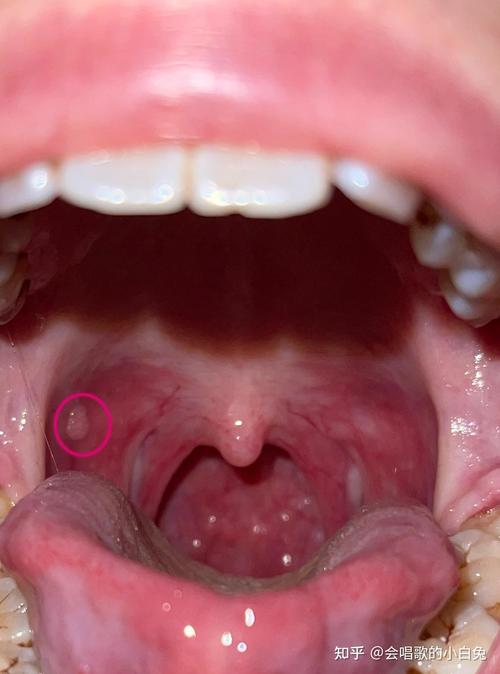

口腔下颚长硬疙瘩是何原因?

- 特点:通常是半透明、柔软或略带韧性的小包,像一颗“水珠”,常见于下唇内侧,但也可能出现在下颚内侧,通常不痛,但有时会因咬到而变大、变硬甚至疼痛。

- 成因:由于唾液腺导管被堵塞,唾液无法正常排出,积聚形成囊肿。

(图片来源网络,侵删)- 特点:通常为淡黄色或白色的小颗粒,成片出现,不高出表面或略微高出,质地柔软,无任何不适感,常见于上唇、颊粘膜,也可能出现在下颚。

- 成因:一种正常的生理变异,不是疾病。

(图片来源网络,侵删)- 特点:在溃疡的愈合阶段,底部可能会形成一个硬结,这是新组织在修复,通常几天后会自行消退。

- 良性肿瘤:如乳头状瘤,通常表面呈菜花状。

- 恶性肿瘤:这是最需要警惕但也是最少见的情况,通常表现为质地坚硬、固定不动、边界不清、生长迅速、表面可能溃烂、出血或伴有麻木感,这种情况多见于中老年人,或有长期吸烟、饮酒史的人群。